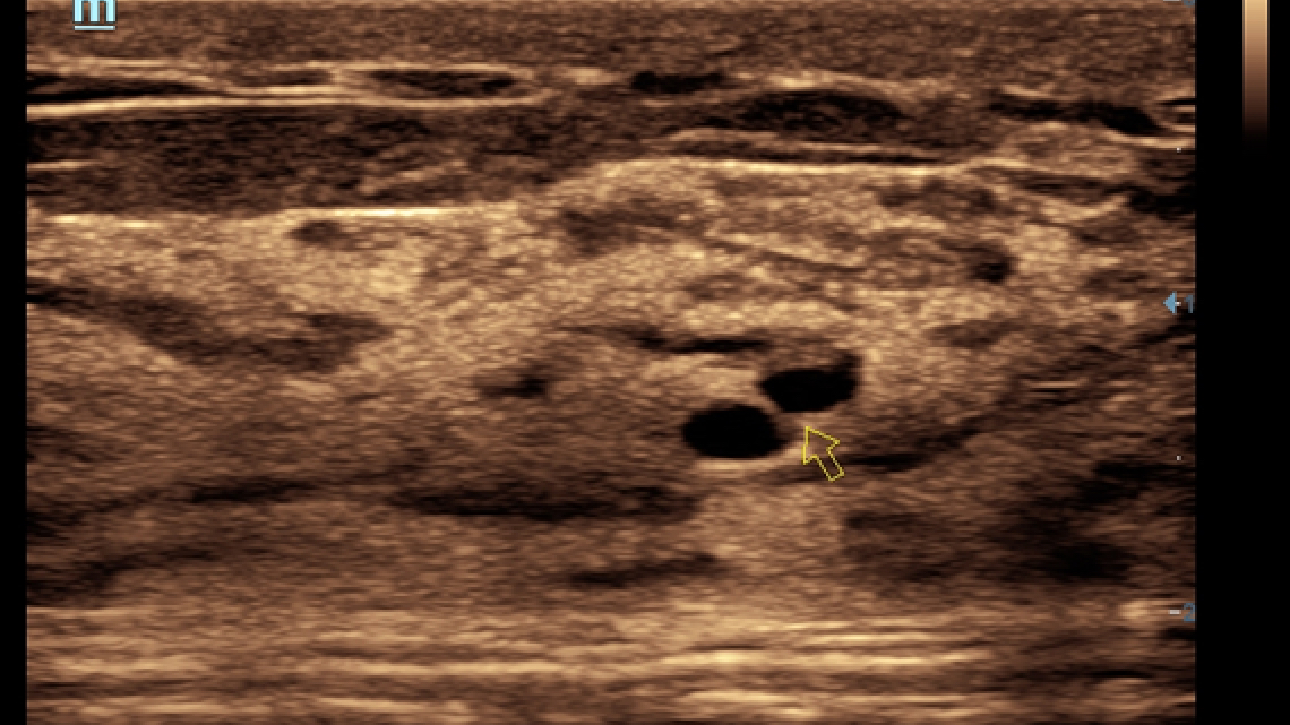

Klinische Bilder